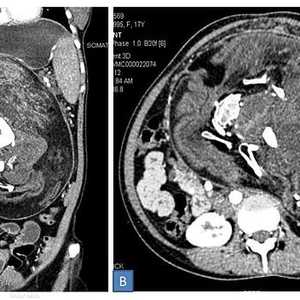

ولدى الأم حالة تعرف باسم "رحم الديلفي"، مما يعني أن كل واحد من التوأمين كان في رحم منفصل.